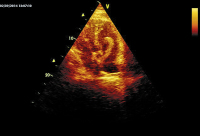

Abbildung 1: Echoreiche Massen in der linken und der (mäßig dilatierten) rechten Kammer.